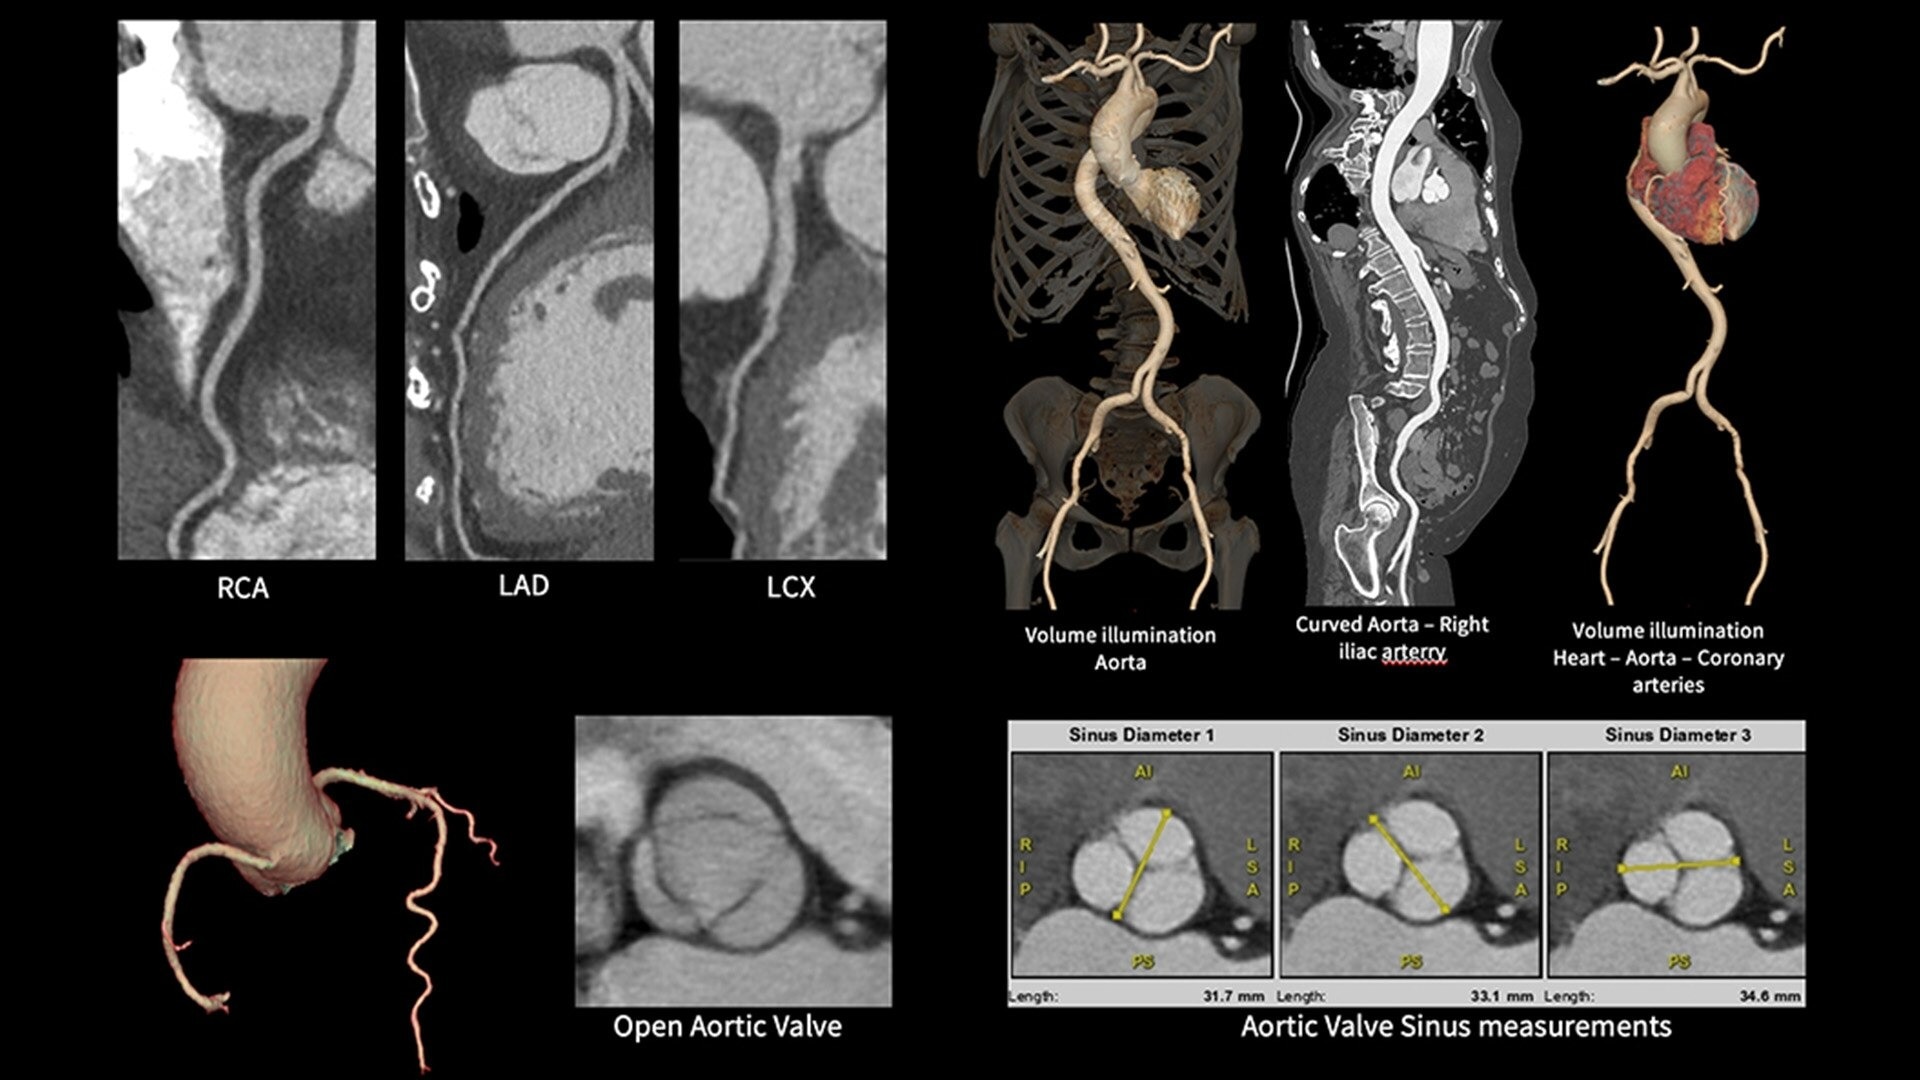

The 160 mm Clarity Detector's z-coverage makes whole-heart coverage in a single axial rotation a reality. This hardware breakthrough provides outstanding image quality for all patients.

Smart Phase is a reconstruction feature designed to intelligently select the best cardiac phase for image reconstruction. This ensures improved image quality with the least motion and enhances workflow by reducing the need for manual phase adjustments.

Snapshot Freeze 2 is an intelligent motion correction algorithm that's designed for coronary and valve motion correction, chambers, myocardium correction and great vessels motion correction.